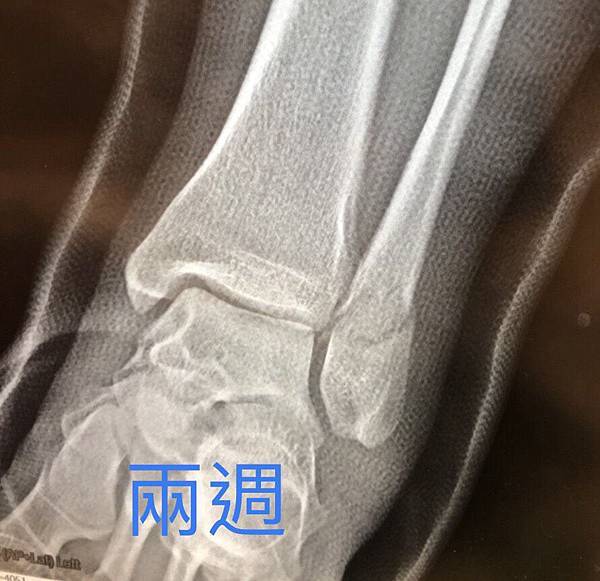

因此,吃兩個禮拜水藥的效果,連放三張讓大家比較,從上到下分別是受傷當天、沒吃藥兩周、吃藥兩周

第四周的照片,靠中心的裂痕明顯糊掉,看來進展不錯